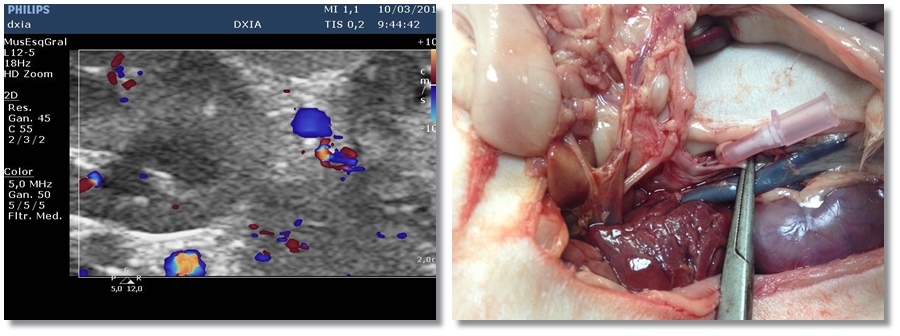

Shunt o Comunicación

Yorkshine terrier de 6 años, de pequeño tamaño, con únicamente ictericia. Analíticamente se observa alteración…